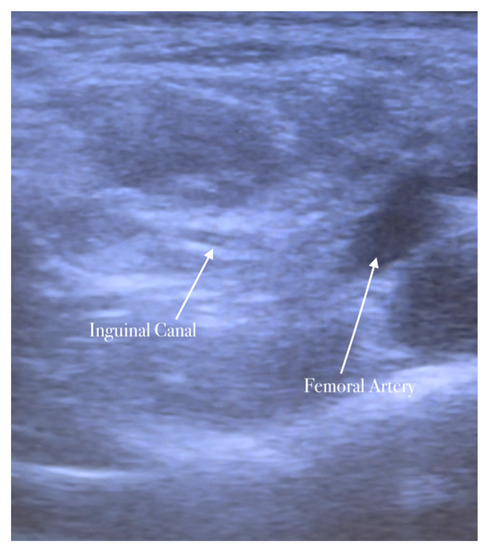

The high-frequency linear probe is initially kept perpendicular to the inguinal ligament just above the femoral vessels. The final position of the probe is about 2 cm lateral to the pubic tubercle. In this position, the femoral artery is identified. The inguinal canal lies above and medially the femoral artery appearing as an oval or circular structure. The probe is then moved slightly in the medial direction away from the femoral artery.

The needle is inserted in the plane in a medial-to-lateral direction; 10 mL of anesthetic is injected in the transversus abdominis plane, as seen in Figure 5, Figure 6 and Figure 7.

Spermatic cord identification.

The anesthetic is injected in the spermatic cord.